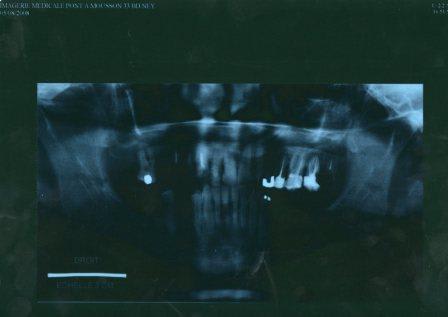

la pano!

Je suis désolée pour la pano qui est plus que moche. Je vous résume la situation:

27 28 14 15 extraites

12 22 cariées en mesial et distal mais vivantes

13 racine

23 incluse

24 25 reprise carie sous amalgames

pathologie paro a un stade assez avancée: homme de moins de 40 ans non fumeur avec tres peu d'hygiene mais qui se motive doucement!

PROGNATIE MANDIBULAIRE